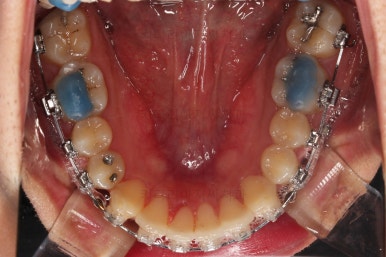

초진 시 입안의 모습입니다.

앞니가 약간 삐뚠 것 말고는 큰 문제는 없어보이네요.

장치를 부착했습니다.

이번 부산연제구교정 환자분이 선택한 장치는 엠파워 클리어라고 하는 자가결찰 세라믹 장치입니다.

최대한 빠른 시일 내에 치열을 가지런하게 해주고 미니스크류를 많이 식립하게 됩니다.